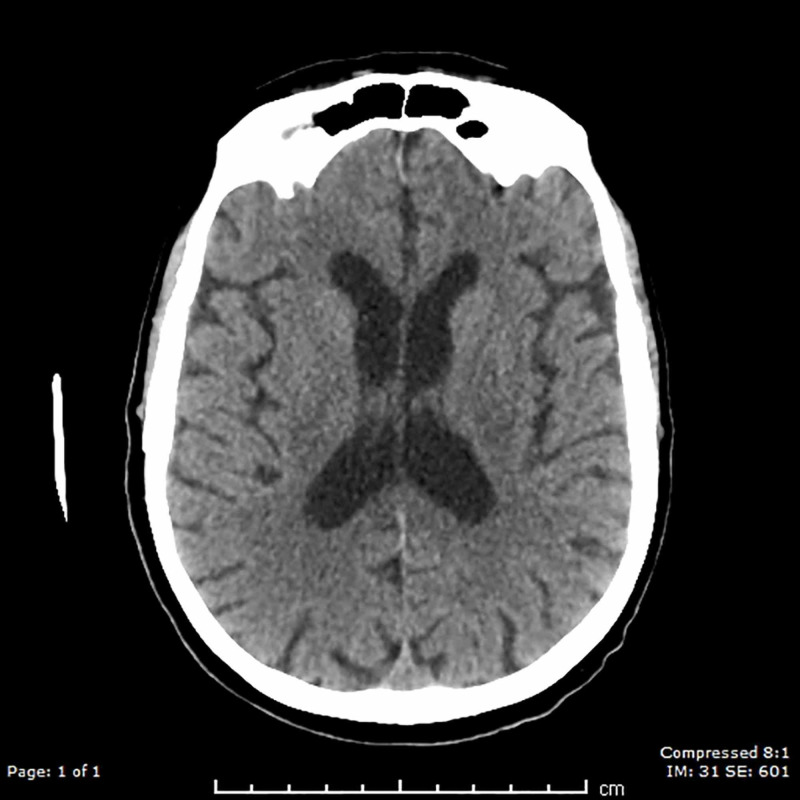

Neurological assessment on day 26 revealed a stuporous patient (Glasgow Coma Scale fluctuating between 3-6) with no physical signs of cranial nerve involvement. In particular, the patient showed no signs of gaze palsy or ptosis. Papilledema was excluded by fundoscopy while light reflex remained intact. There were no meningeal signs such as neck stiffness or a positive Kernig’s sign. He underwent tracheostomy on day 27 as he was not improving and pneumonia symptoms were worsening. He underwent a CT scan of the brain on day 28, showing no discernible structural abnormalities (Figure 3).

Figure 3. CT brain demonstrating normal findings .

Normal CT scan of the brain showing severe diffusion restriction of the MRI brain. The normal recovery after the prolonged hospital stay confirmed it was unlikely that the severe neurological and stroke-like symptoms were due to a stroke.